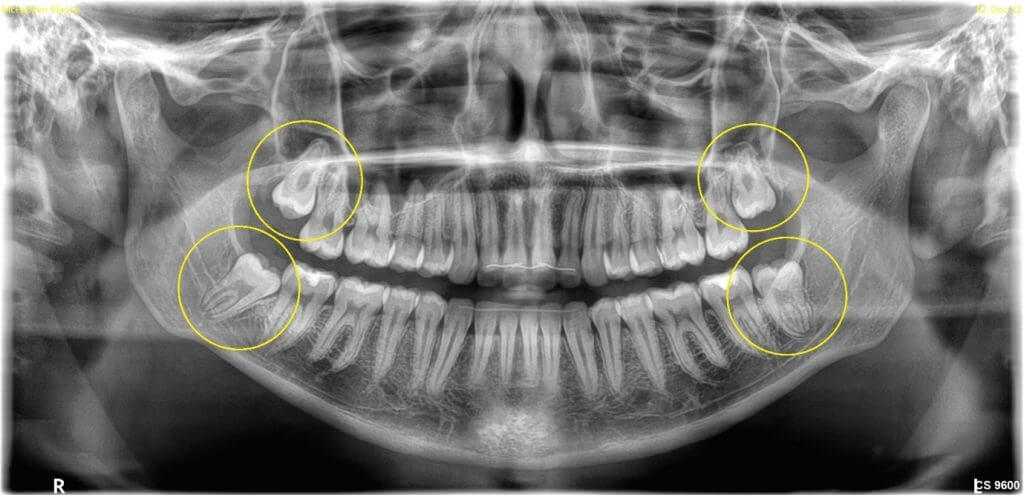

Wisdom teeth are the last to emerge in the mouth and often have little space in the jawbone to erupt fully in an upright position, leading to impaction (as shown in the panoramic X-ray below).

Panoramic X-ray showing top and bottom teeth, with impacted and unerupted upper and lower wisdom teeth.